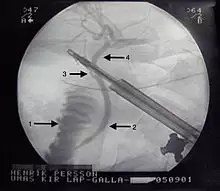

This is a cholangiogram, an x-ray of the bile ducts using contrast medium to make the bile ducts visible. 1 - Duodenum. 2 - Common bile duct. 3 - Cystic duct. 4 - Hepatic duct. The gallbladder is not seen as the cystic duct is occluded by a surgical instrument.

ERCP, short for endoscopic retrograde cholangiopancreatography, is an endoscopic procedure that can remove gallstones or prevent blockages by widening parts of the bile duct where gallstones frequently get stuck. ERCP is often used to retrieve stones stuck in the common bile duct in patients with gallstone pancreatitis or cholangitis. In this procedure, an endoscope, or small, long thin tube with a camera on the end, is passed through the mouth and down the esophagus. The doctor advances the camera through the stomach and into the first part of the small intestine to reach the opening of the bile duct. The doctor can inject a special, radiopaque dye through the endoscope into the bile duct to see stones or other blockages on x-ray.[45] ERCP does not require general anaesthesia and can be done outside of the operating room. While ERCP can be used to remove a specific stone that is causing a blockage to allow drainage, it cannot remove all stones in the gallbladder. Thus, it is not considered a definitive treatment and people with recurrent complications from stones will still likely need a cholecystectomy.